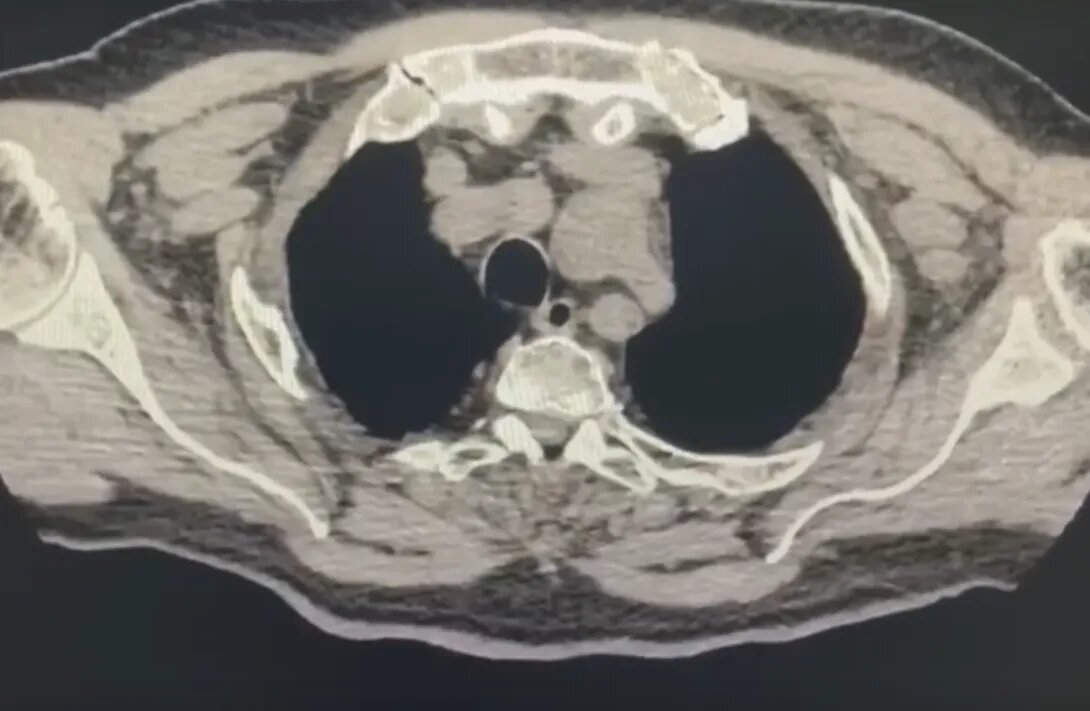

У пенсионера диагностировали расслаивающуюся аневризму дуги аорты. Патология могла спровоцировать кровотечение. С жалобой на отдышку 75-летний воронежец обратился в БСМП №1. Также его беспокоили боли в сердце и низкое давление. Подробное обследование выявило всю тяжесть состояния мужчины. При этом уже во время госпитализации у пенсионера внезапно остановились дыхание и сердце. К счастью, реанимация оказалась успешной. После стабилизации пациента медики провели операцию – врачи полностью заменили весь участок расслоенной аорты и часть дуги, а также устранили нарушения в работе клапана. «Во время такой операции вместо сердца и легких работает аппарат искусственного кровообращения, обеспечивая кровью все органы, но на определенном этапе операции необходимо полностью на 20-40 минут остановить кровоток по сосудам (циркуляторный арест). Специалисты выполнили очень важную задачу – спасли все органы и системы организма от ишемии», - рассказали в региональном минздраве. Операция длилась семь ч

У пенсионера диагностировали расслаивающуюся аневризму дуги аорты. Патология могла спровоцировать кровотечение.

С жалобой на отдышку 75-летний воронежец обратился в БСМП №1. Также его беспокоили боли в сердце и низкое давление. Подробное обследование выявило всю тяжесть состояния мужчины. При этом уже во время госпитализации у пенсионера внезапно остановились дыхание и сердце. К счастью, реанимация оказалась успешной. После стабилизации пациента медики провели операцию – врачи полностью заменили весь участок расслоенной аорты и часть дуги, а также устранили нарушения в работе клапана.